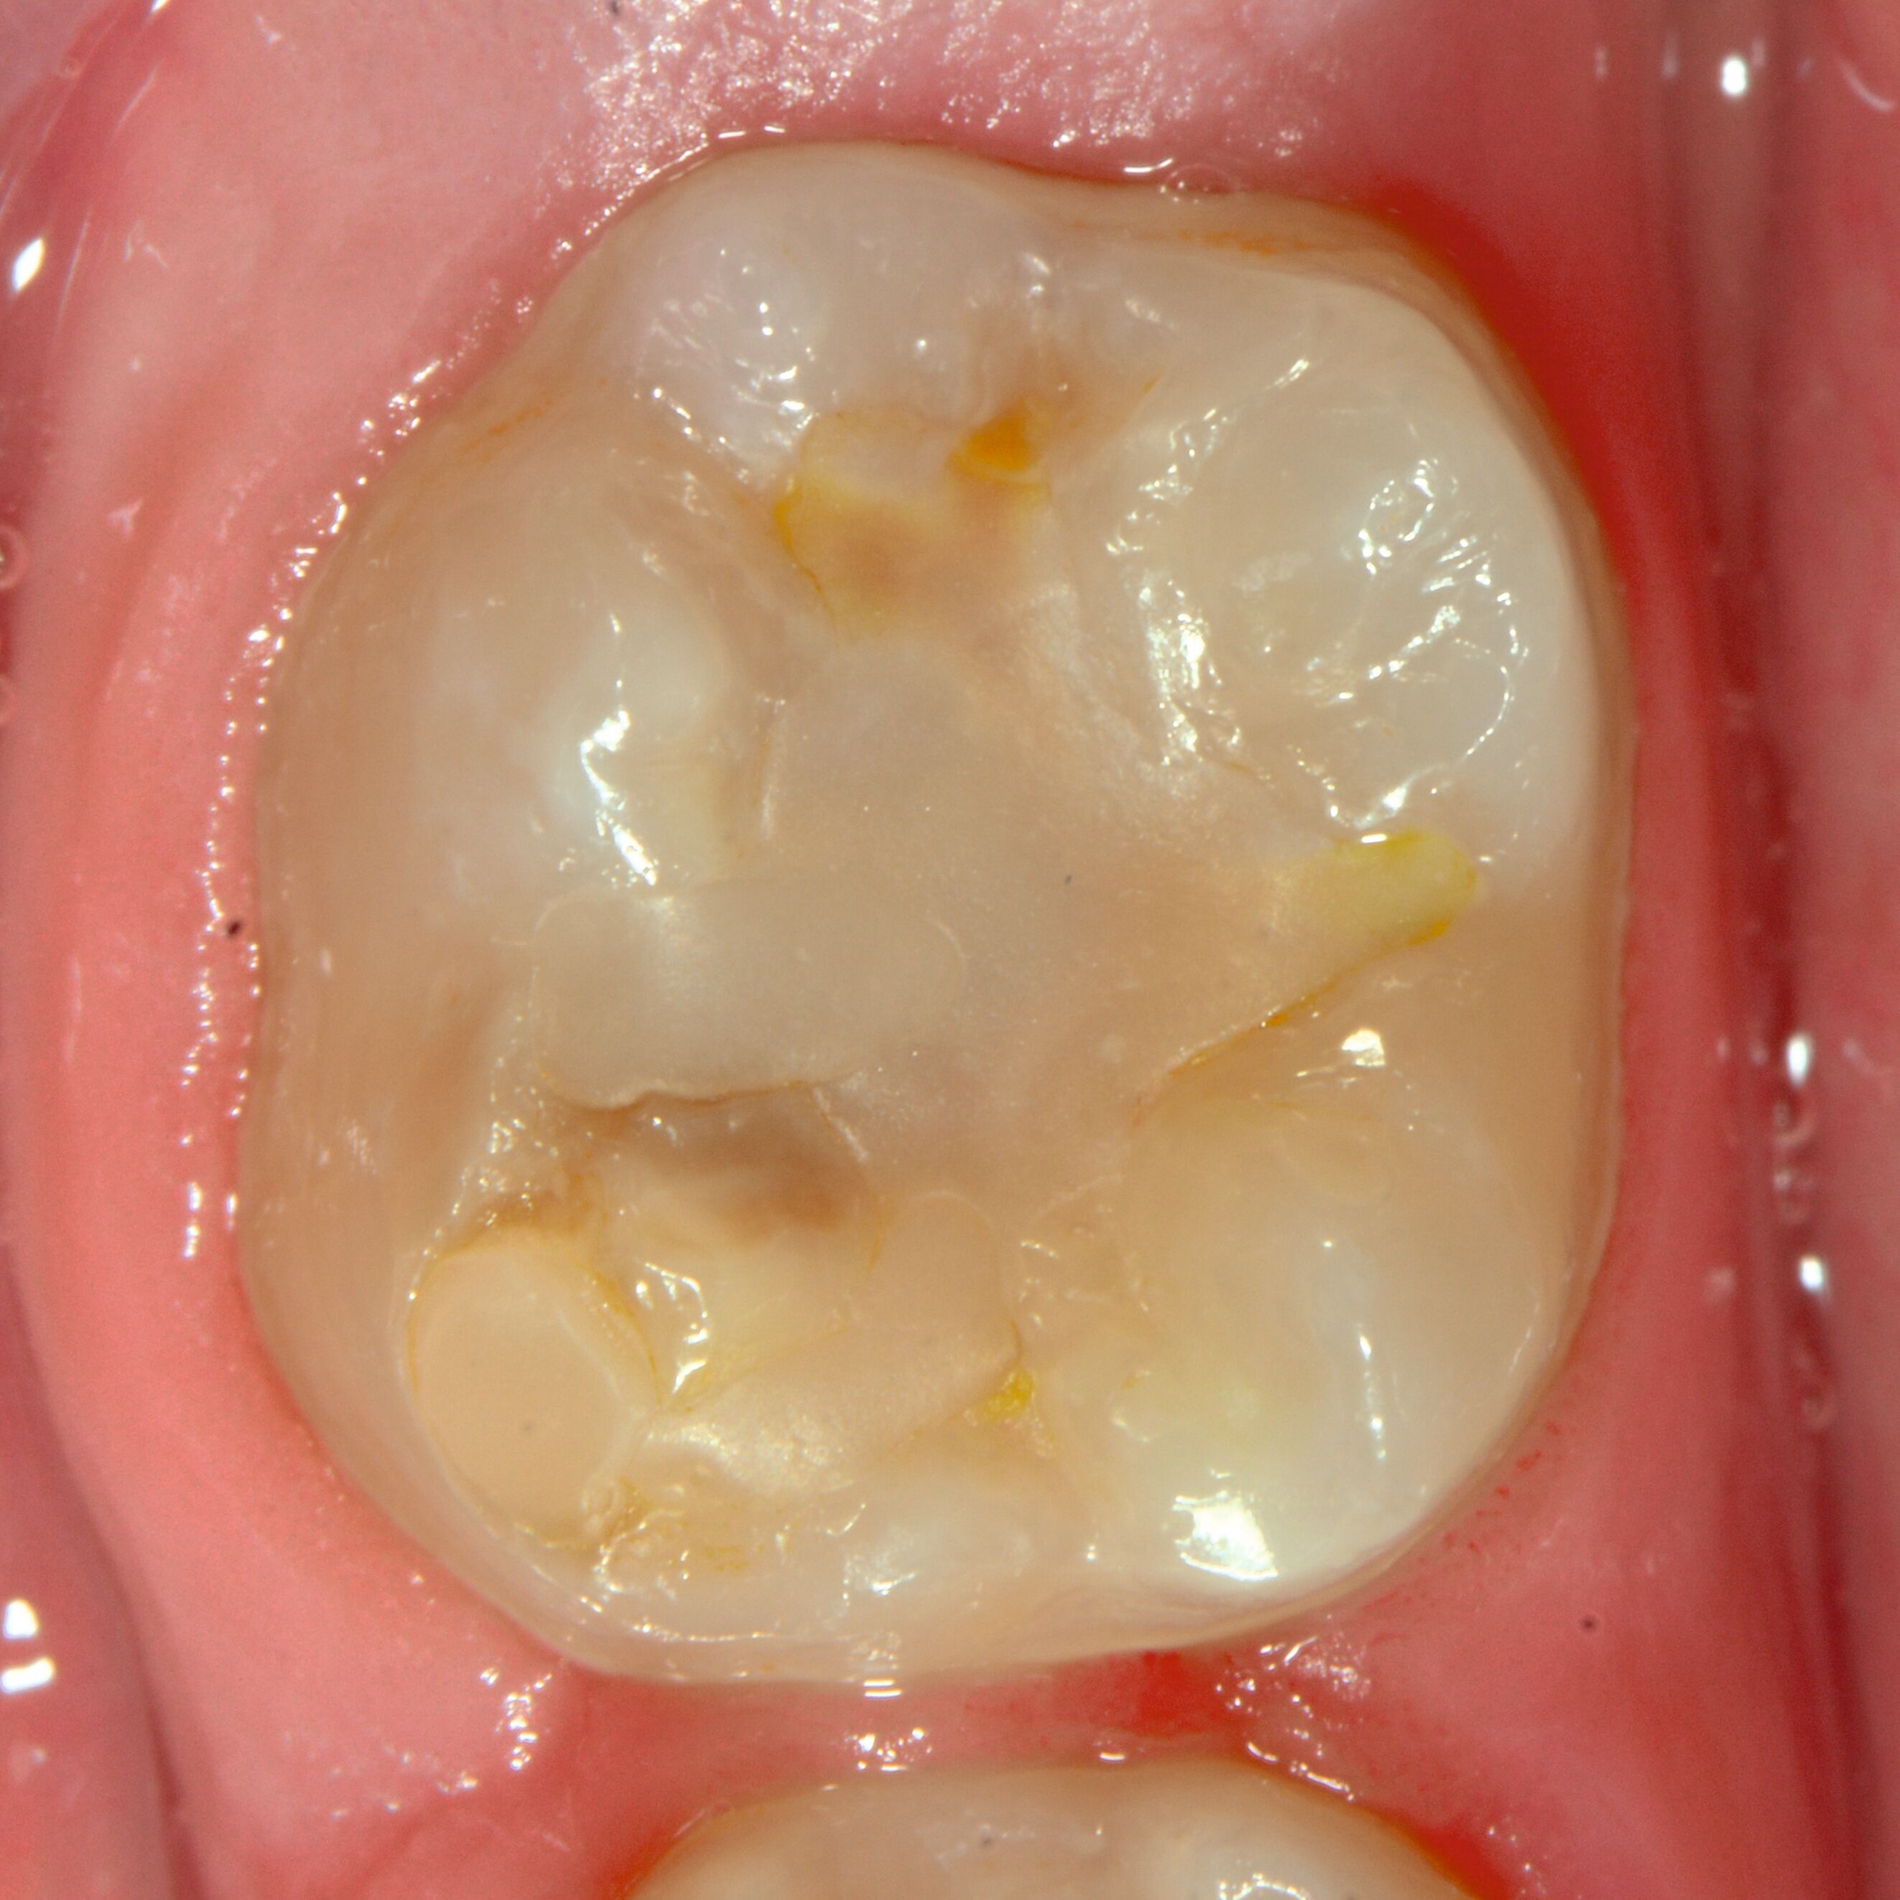

Das klinische Erscheinungsbild an bleibenden Zähnen zeigt typischerweise weißlich-gelbe bis gelblich-braune Opazitäten, die zumindest in einigen Bereichen durch eine scharfe Abgrenzung (engl.:„demarcated opacities“) zum gesunden Zahnschmelz charakterisiert sind (Abbildungen 3 und 4). Die abgegrenzten Hypomineralisationen befinden sich mehrheitlich im Bereich der inzisalen Kronenhälfte unabhängig von dem Auftreten an Front- oder Seitenzähnen. Die Ausprägung am Zahn kann dabei auf einzelne Areale oder Höcker begrenzt sein.

Bei einer schwerwiegenderen Ausprägung sind Zahnflächen vollständig betroffen, mitunter alle Zahnflächen an einem Zahn. Die Verteilung in der Dentition beziehungsweise an den Indexzähnen ist gleichermaßen variabel und betrifft nicht nur die Defektgröße, sondern auch die Farbe und Festigkeit. Was die Festigkeit betrifft, gilt als die Faustregel: Je dunkler die Farbe des Schmelzes, umso weicher beziehungsweise poröser und damit minderwertiger wird dessen Qualität sein. Damit reduziert sich seine kaufunktionelle Belastungsfähigkeit, was insbesondere an ersten bleibenden Molaren von klinischer Relevanz ist.

Für die Dokumentation und Klassifikation der MIH wurden verschiedene Systeme vorgeschlagen. Als historisch und veraltet gilt der (modifizierte) DDE-Index. Demgegenüber haben die Kriterien der EAPD – abgegrenzte Opazitäten (Abbildung 3 und 4), Schmelzeinbrüche (Abbildung 5), atypische Restaurationen (Abbildung 6) – mittlerweile die weiteste Verbreitung gefunden. Diese wurden 2003 erstmals zur Beschreibung der MIH auf empirischer Basis publiziert [Weerheijm et al., 2003] und den Jahren 2010 und 2022 im Rahmen der damaligen MIH-Workshops bestätigt [Lygidakis et al., 2010; 2022].